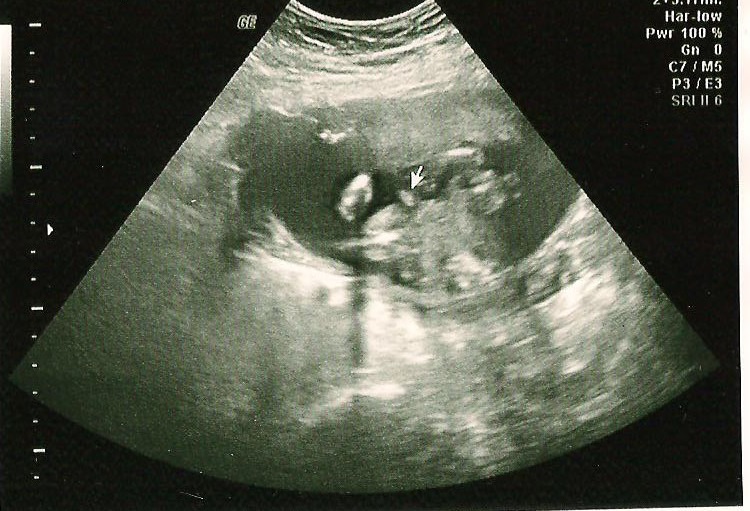

I had my anatomy scan last Tuesday and the doctor told me that he was 95% sure that it was a boy. My husband and I were thrilled to get this news after two girls. At first they were a little doubtful that it was a boy because the umbilical cord was between the legs also but after looking some more confirmed that it was indeed a he. The doctor kept going on about because 95% sure like a mentioned but then the ultrasound tech said to keep the recipts just in case....now it's all in my head...and I am really doubting it. I will attach a picture that is suppose to be his boy parts. Attachment 11686